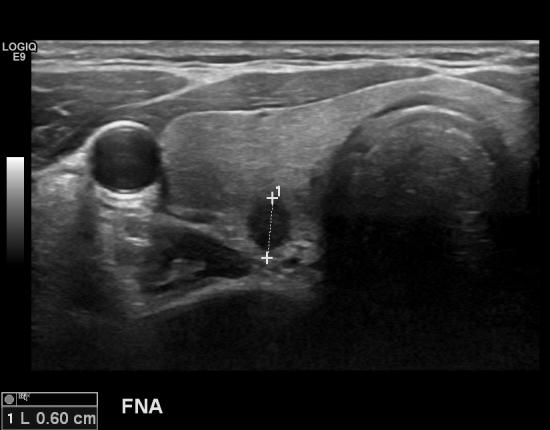

목이 불편해서 내원하셨다가 갑상선 초음파를 시행한 30대초반

남자분입니다.

어머님이 갑상선암이 진단되셔 치료하신 가족력이 있었습니다.

여자만 갑상선암에 걸리지는 않습니다.

가족력이

있거나 증상이 있으면

갑상선초음파로 이상여부 관찰이 필요하리라 여겨집니다.